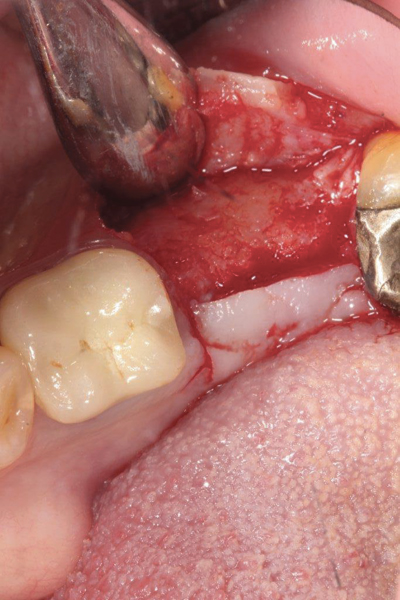

Fig 2. Buccal flap elevated exposing buccal plate defect.

Figure 2